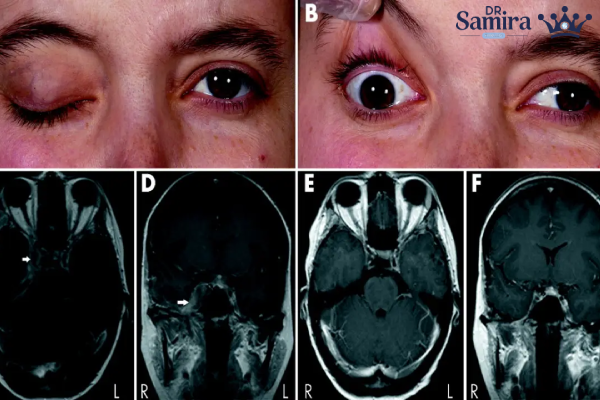

تظاهرهای بالینی مننژیوم سینوس کاورنوس تدریجی و پیشرونده است. نخستین علامتی که بسیاری از بیماران تجربه میکنند، اختلالات چشمی است. دلیل آن است که اعصاب کنترل کننده حرکات چشم در مجاورت مستقیم سینوس کاورنوس عبور میکنند. اختلال در عملکرد این اعصاب میتواند منجر به دوبینی، مشکل در حرکت دادن چشم، افتادگی پلک یا اختلال در حس ناحیه پیشانی و گونه شود.

فلج عصب ششم مغزی

یکی از مهمترین علائم، فلج عصب ششم مغزی است؛ زیرا این عصب بسیار حساس بوده و تحت فشار تومور بهسرعت عملکرد خود را از دست میدهد. برخی بیماران نیز احساس درد در ناحیه اوربیتال یا شقیقه دارند که ناشی از درگیری شاخههای اعصاب سهقلو است. اگر تومور به سمت شبکه وریدی گسترش یابد، ممکن است پف کردن اطراف چشم یا اختلال جریان خون ایجاد شود.